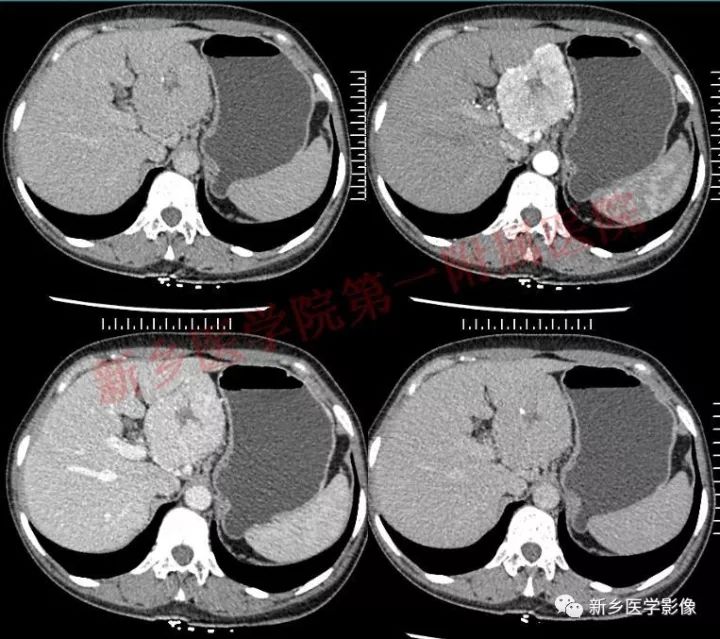

肝胃间胰腺前上方见类圆形肿块,边界较清,大小约8.2cm×4.6cm×5.9cm,密度欠均匀,内见点状钙化,增强呈不均匀明显强化,内见片状低密度灶无强化区,其下部与相邻胰腺分界不清,周围见粗大回流血管影回流至门静脉,病变左侧及腹膜后、胃壁小弯侧见数个卵圆形稍大淋巴结及结节影,部分呈环形强化。

GLNH高强化机制为透明血管型病灶内丰富的毛细血管增生和周边较多粗大的滋养动脉所致。

GLNH钙化较少,可见于5%~10%的病例,且仅见于局限型透明血管型。

GLNH另一个特征是瘤灶内极少伴有出血和坏死灶,尽管部分病例呈不均匀性强化,但瘤灶内的低密度影并非坏死灶。